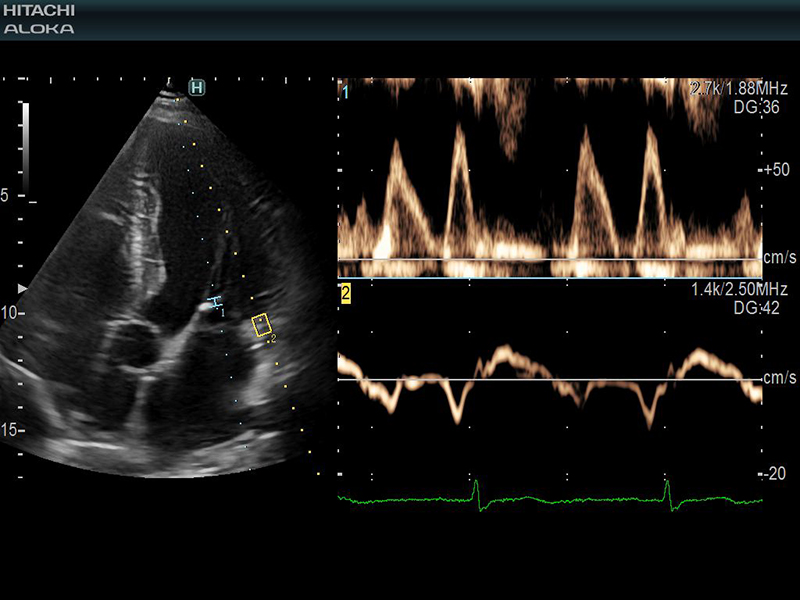

- Rối loạn nhịp tim: Tiếng vang cho phép đánh giá nhịp tim, giúp xác định nguyên nhân chính xác và cách điều trị tốt nhất cho tình trạng nhịp tim không đều.

Nhịp tim được hiển thị rõ ràng trên hình ảnh siêu âm tim